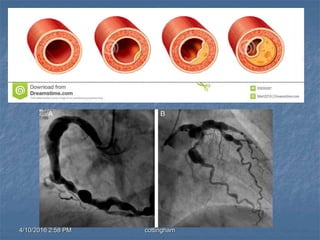

Cardiac Angiography

4/10/2016 2:58 PMcottingham Valves VALVES  Atrioventricular – allows blood to flow between atria and ventricle  Semilunar – allows blood to flow from ventricles Cardiac Angiography